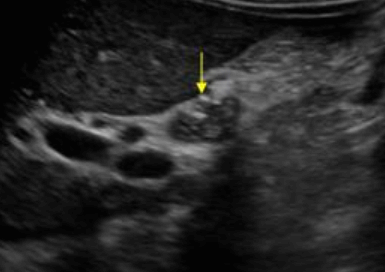

간내담관암(intrahepatic cholagiocarcinoma) ▣ 간문부 담관암(Klatskin's tumor = Hilar cholagiocarcinoma)

- 좌우 간내담관이 갈라지는 간문부에서 발생하는 암이다.

- 담관암의 50%를 차지한다.

- 대부분의 환자는 폐쇄성 황달을 일으킨다.

US finding

- 간내담관은 확장되고 간외담관은 정상이다.

- 담낭은 위축되며, 간외담관은 담즙 흐름이 없는 담관으로 묘출된다.

- 폐쇄된 담관부위에 종양의 윤곽이 보일 수 있으나 초음파상 발견하기 어렵다.